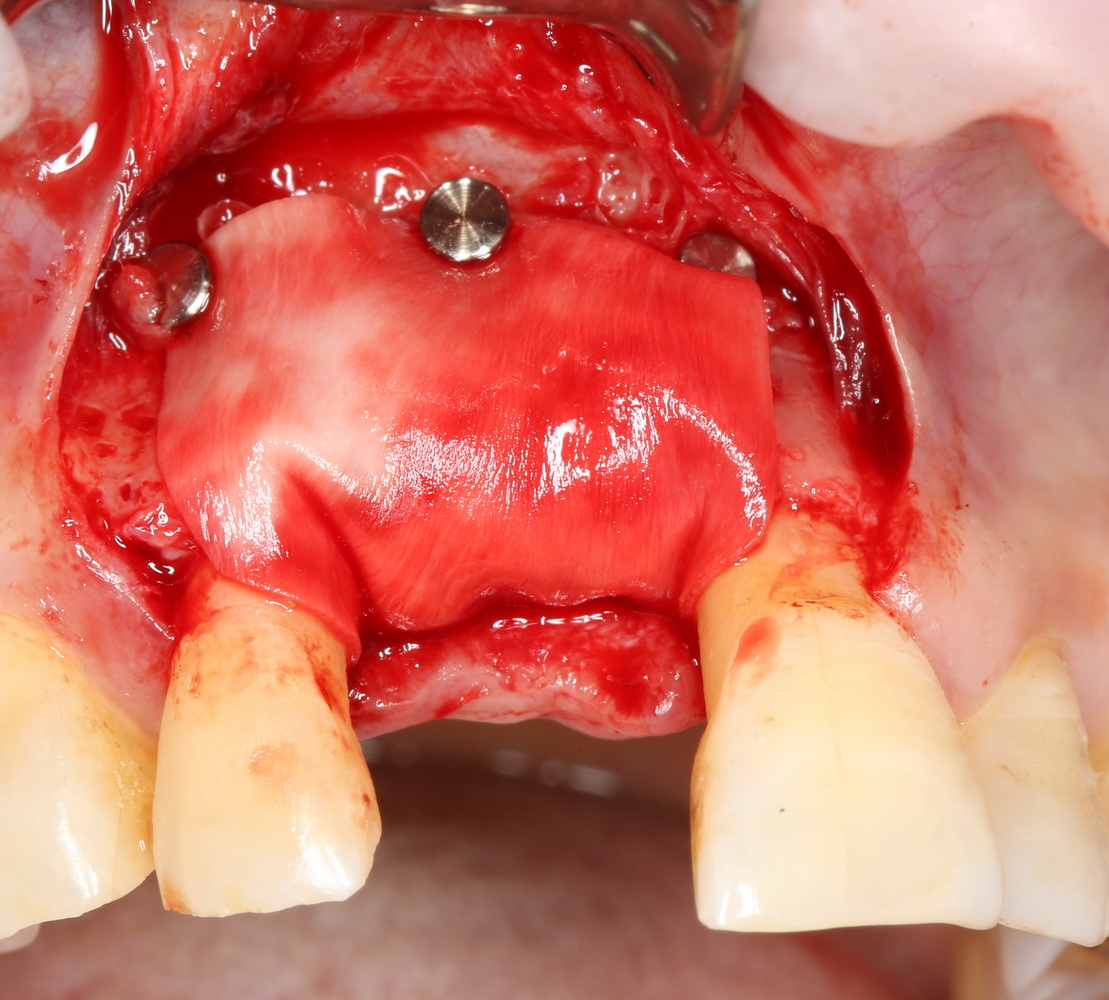

В этом случае остеопластика делается отдельной процедурой. Ее принципы точно те же, но уже без импланта. Например:

Имплантировать в таких условиях — заведомо обрекать себя на хреновый, с точки зрения эстетики и функциональности, результат. Поэтому первым этапом проводим остеопластику. Объем небольшой, использовать в таких объемах костный блок не очень рационально. Воспользуемся аутокостной стружкой и мембраной.

Сначала фиксируется BioGide. Это легко:

Затем укладывается и конфигурируется аутокостная стружка:

Если после этого BioGide намочить физраствором, им легко укрыть получившийся объем:

Для надежности можно зафиксировать пинами:

Ну и, швы: